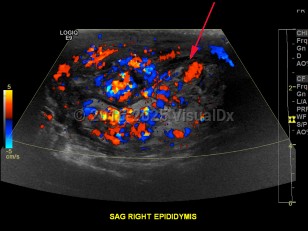

Epididymo-orchitis

Symptoms of epididymo-orchitis usually develop over 1-2 days, although some patients will complain of a more gradual onset of symptoms. The primary complaint is swelling of the scrotum associated with pain. Urethral discharge is common. Fever may or may not be present. On palpation, swelling in the posterior scrotum localized over the involved epididymis can be appreciated. There may be a hydrocele. There may be erythema overlying the area of swelling. Pain should improve within 72 hours after treatment, although inflammation may persist for a few weeks.